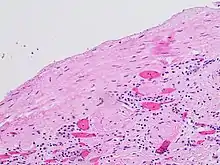

The complex cyst can be further evaluated with doppler ultrasonography, and for Bosniak classification and follow-up of complex cysts, either contrast-enhanced ultrasound (CEUS) or contrast CT is used.[12]